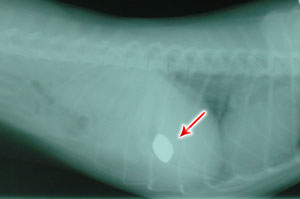

Scipio's X-RayThe man, obviousely shaken, started to mumble a few incoherent words to Dr. Ghazi, when we heard the Nurse call Dr Ghazi saying "Doctor, you got to see this!". She was reffering to the X-Ray just taken from the cat (see picture). "What can be in the cat's stomach?" Wondered Dr. Ghazi. It must be metallic as it has absorbed a lot of the X-rays (appears white on image). "We must prepare the cat for emergency surgery" said Dr Ghazi. "He has ingested something like a wire".

About an hour passed before Dr. Ghazi came out of the operating room with his usual smile, holding Scipio who was still asleep in a recovery box. "You won't believe this!" muttered Dr Ghazi, "Look what I found in his stomach!" he said while holding a telephone cord in his left hand (see picture).